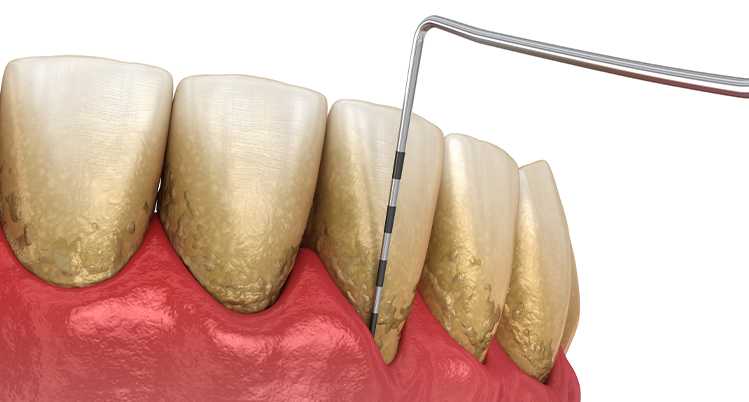

1. 歯周ポケットの深さを測定

専用の器具を使って歯ぐきの深さを測る検査です。定期健診などで行っている歯ぐきの検査と同じです。歯ぐきの深さを測るため少しチクチクと痛みを感じる方もいます。

1本の歯につき4~6か所測定します。

• 0~3mm 正常、歯肉炎、または軽度

• 4~6mm 中等度歯周炎

• 7mm以上 重度歯周炎

歯周病検査を受けている様子